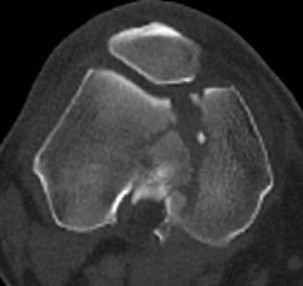

Type C: Complete articular

Xray / CT